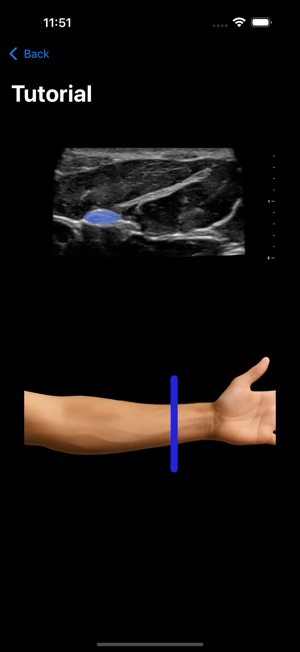

MSK VUE is a specialized training application for musculoskeletal ultrasound. The system utilizes an artificial intelligence component to support the identification of key peripheral anatomical structures within an interactive, simulated ultrasound imaging environment. The interface is designed to present visualizations of nerves, tendons, and bones, allowing users to engage with the simulated data. This application's core mechanism focuses on presenting specific anatomical targets and facilitating their recognition through its AI-driven framework, providing a platform for practice in a non-clinical context.

This application is designed for clinicians seeking to develop proficiency in musculoskeletal ultrasound. It functions as a supplementary educational tool for practicing the identification of peripheral anatomical structures within a simulated environment. This app is intended for educational purposes and does not replace professional medical advice, diagnosis, or treatment; the provided description explicitly prohibits its use in any clinical setting or for any clinical purposes.